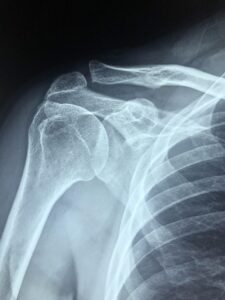

Arthritis in the Ball and Socket Joint Arthritis is actually relatively uncommon in this joint. But when it occurs it tends to show a distinct pattern. The hallmark of arthritis at the ball and socket shoulder joint is joint space narrowing bone spurs at the bottom of the ball portion of the joint. The patient … Read more

Categories Orthopedics, Shoulder Arthritis, Shoulder Problems and Treatments, Shoulder Replacement Tags Updated